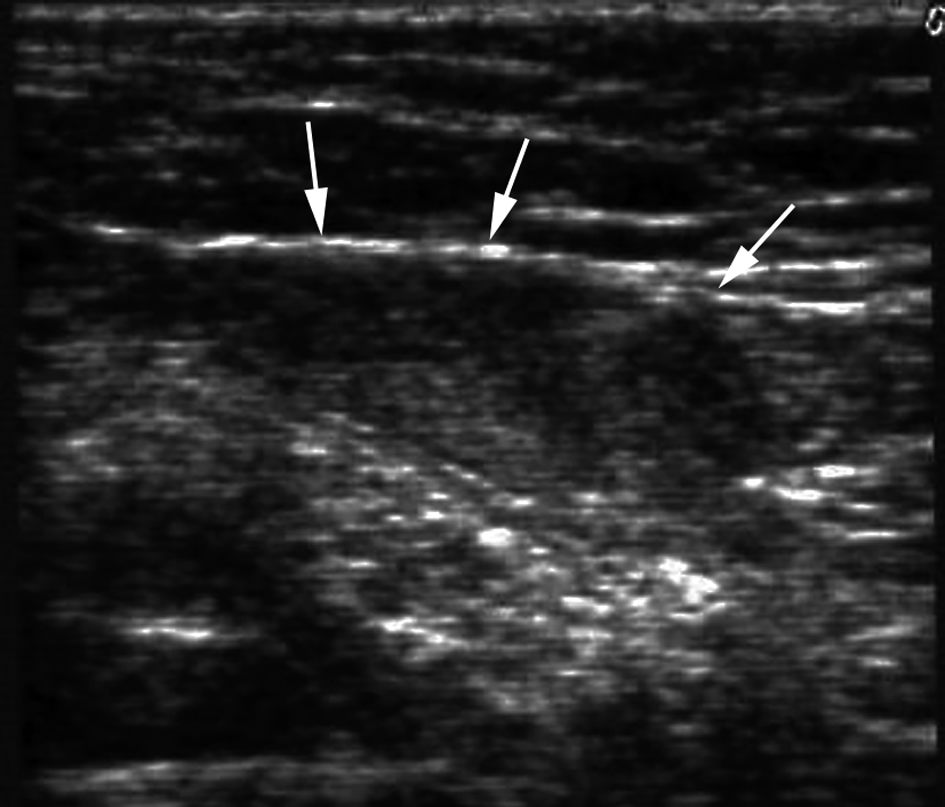

A. Échographie abdominopelvienne

Lorsque le testicule n’est pas palpable, l’échographie peut permettre de le repérer.

Le testicule cryptorchide est de petite taille, hypoéchogène, hétérogène, surmonté d’un épididyme d’aspect habituel ou diminué de taille (figure 28.5).

Fig. 28.5. Échographie, plan sagittal.

Petit testicule dans le canal inguinal hypoéchogène et hétérogène (flèches).

Source : CERF, CNEBMN, 2022.

Après correction chirurgicale de la cryptorchidie, le testicule reste hypoéchogène hétérogène. Le signal doppler intratesticulaire est absent ou très faible. L’échographie recherche une masse tumorale testiculaire.